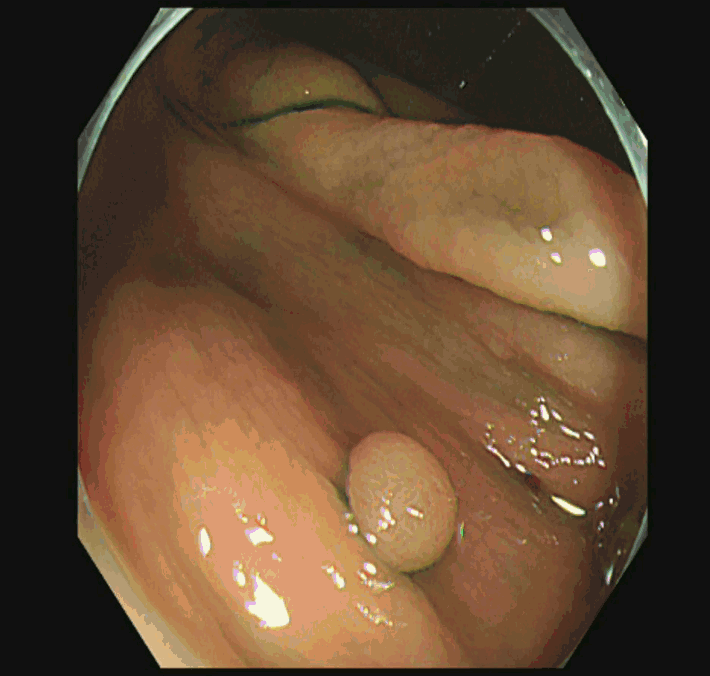

実際の「Extended Cold法」の模様を紹介します

しかしながら・・・いつも、このような綺麗な「目玉焼き」ができる訳ではありません。実際はスネアー(ワイヤー)が、うまくかからずに「分断」「分割」になったり、カンシ(ジャンボ・バイオプシー)を併用することも多いです。